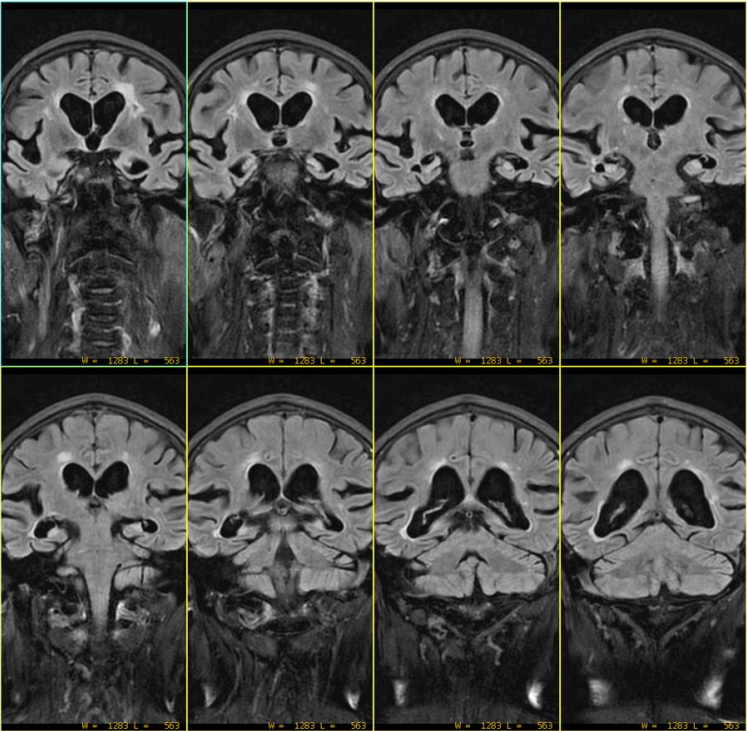

回顾本病例,AX DWI定位线如下: